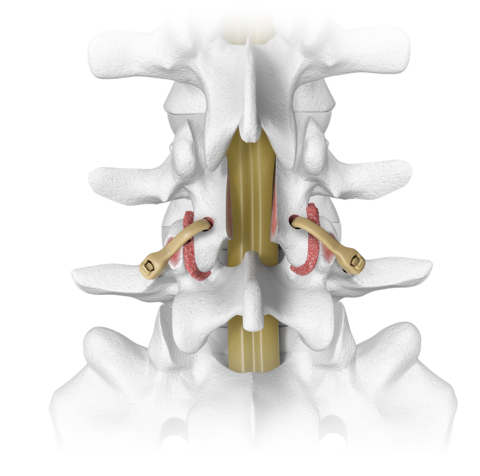

The Karma system consists of a high-performance polymer fixation device used to stabilize the lumbar spine as an adjunct to fusion procedures. It is designed to engage the strongest bony elements of the posterior lumbar spine. Given its polymer construction, the device is radiolucent with the exception of a blended contrast medium that allows Karma to be seen radiographically. Otherwise, the device does not interfere with postoperative imaging.

The Karma device may be surgically implanted through open or minimally invasive surgical techniques, and its extremely low device profile compared favorably to other larger metal posterior fixation devices. The system is part of Spinal Elements’ MIS Ultra™ suite of products that are intended to address the unintended consequences of spine surgery.

“When a patient presents with a chief complaint of neurogenic claudication, a stable spondylolisthesis and a secondary complaint of mild to moderate low back pain, Karma provides an ideal, less invasive solution and in many cases can be performed outpatient,” said Terrence Crowder, MD, of Sonoran Spine.